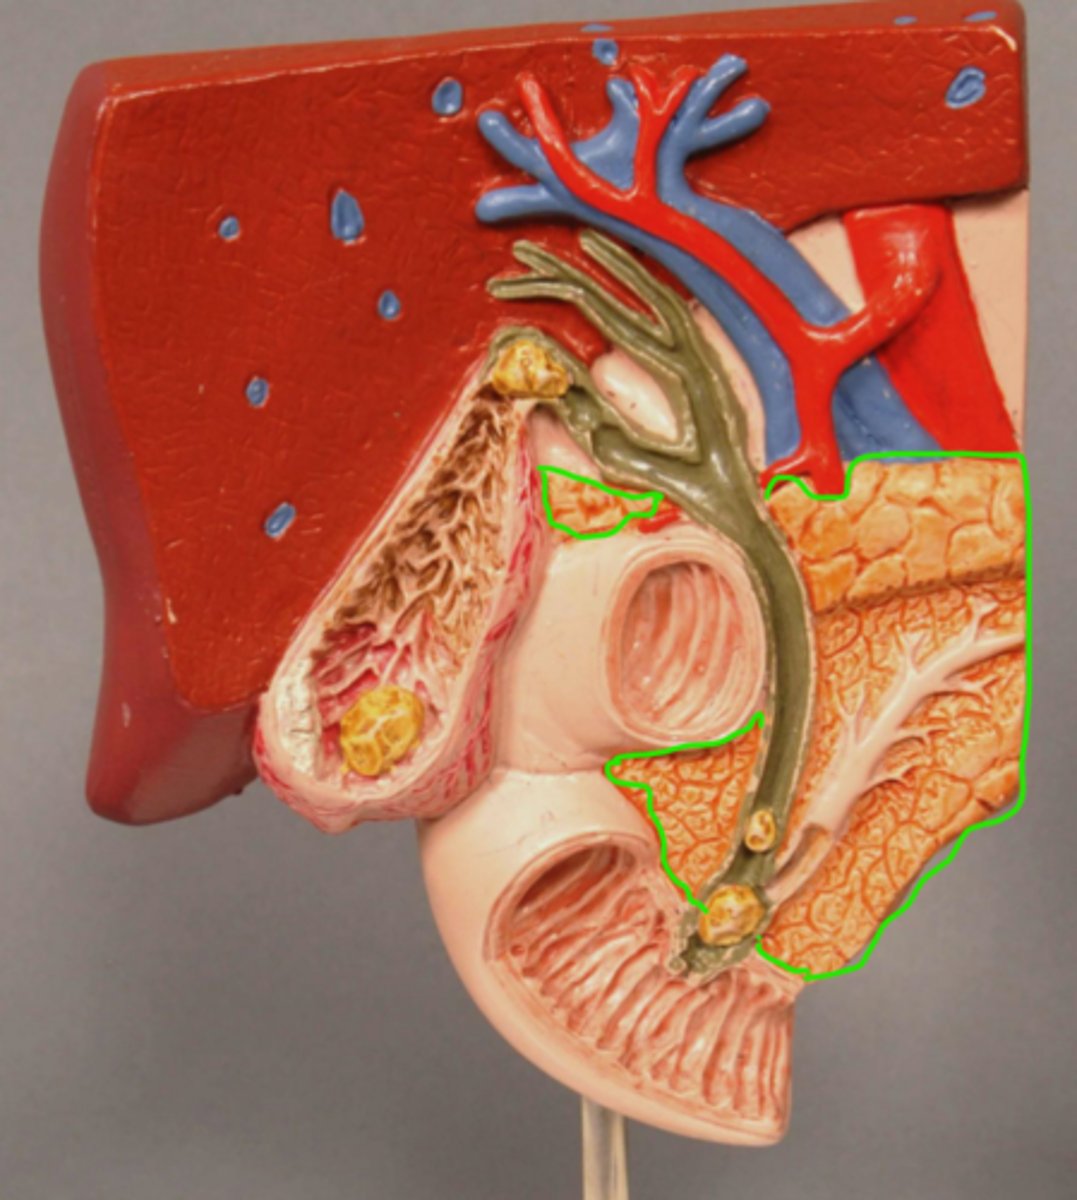

Pancreas

plicae circulares

Duodenum

Sphincter of Oddi

Gallstone in Ampulla of Vater

Gallstone in Bile Duct